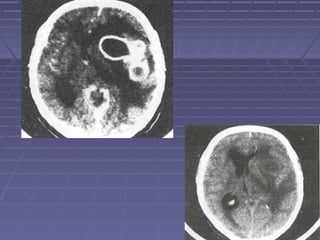

 TAC de cráneoTAC de cráneo si: persisten o aumentan lassi: persisten o aumentan las

manifestaciones clínicas, se sospechamanifestaciones clínicas, se sospecha

herniación, persiste la fiebre.herniación, persiste la fiebre.

 TC: hidrocefalia, lesiones vasculares,TC: hidrocefalia, lesiones vasculares,

tuberculomastuberculomas